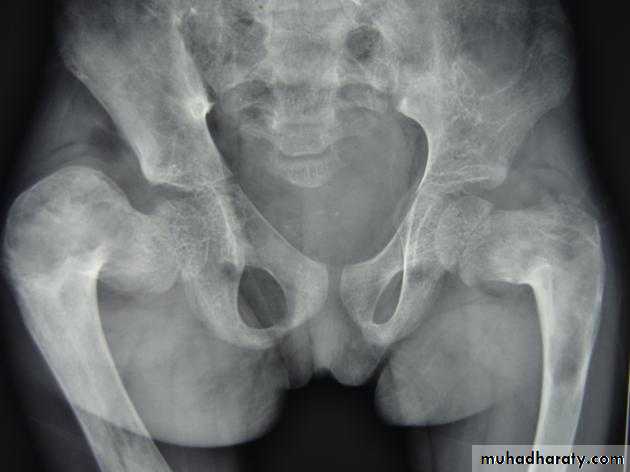

*Legg-Calve-Perthes disease osteochodrosis of the femur head

*Mushroom deformity of femoral Neck (perthes diseade )• *Scheuermann's disease : (adolecent Kyphosis) osteochodrosis of the vertebral end plates

• * Psueodoarthrosis of the femoral head with iliac bone (old neglected CDH)